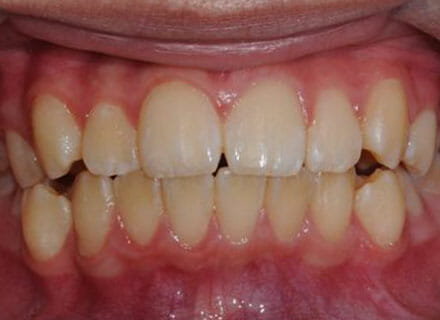

Fixing protruding teeth upper and lower and crowding – no extractions

this patient didn’t like the teeth because they pushed forwards and were sticking out and pushing out her lips. She thought that she looked like she had too many teeth and not enough space. In 12 months we pulled all the teeth back, pulled them together, and lined them all up. No teeth were extracted because we made room by expanding the jaws.